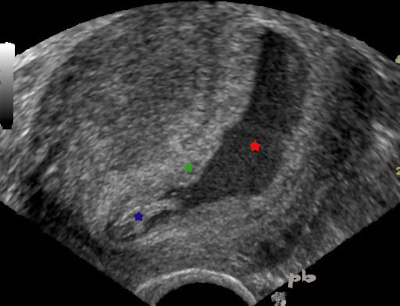

3-GEU – Pseudo sac gestationnel

- Présence de sang dans la cavité utérine = hématométrie (★).

- La paroi de la cavité est hyperéchogène (★) et correspond à la caduque. Il n’y a pas de trophoblaste.

- L’ensemble forme l’image de pseudo-sac.

- En inférieur, proche de l’isthme, présence de caillots (★) intra-cavitaires.